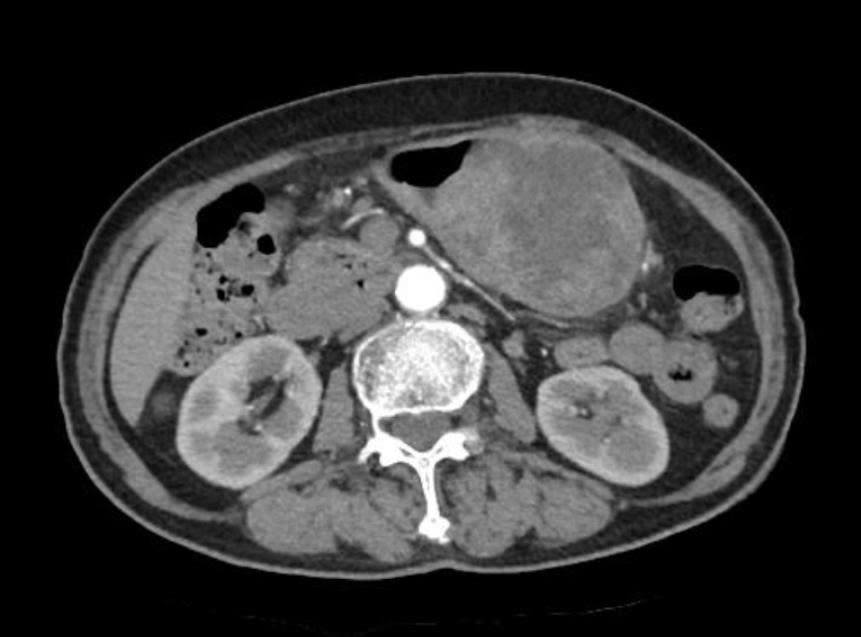

Hình ảnh chụp CT khối ung thư hang vị dạ dày

Người bệnh N.T.N (83 tuổi, Hưng Yên) nhập viện Bưu điện trong tình trạng đau tức vùng thượng vị, chậm tiêu, gầy sút cân rõ rệt trong khoảng một tháng gần đây. Qua thăm khám lâm sàng, nội soi dạ dày, sinh thiết tổn thương và chụp cắt lớp vi tính ổ bụng, các bác sĩ xác định người bệnh bị ung thư hang vị dạ dày, khối u đã xâm lấn qua thành dạ dày và di căn đến một số hạch bạch huyết vùng lân cận.